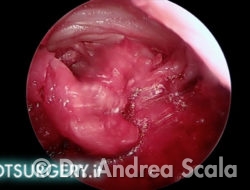

Osserviamo la parte posteriore del calcagno. Nella parte superiore si vedono il tendine d’achille ed i residui della borsite. In basso si vede la parte del calcagno dopo la resezione della sporgenza. Dall’osso tagliato esce un pò di sangue. Sulla destra l’inserzione del tendine d’achille sul calcagno.